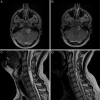

Bilateral vestibular schwannomas are the hallmark of neurofibromatosis type 2 (NF2), and these tumors impair hearing and frequently lead to deafness. Neurosurgical intervention, the only established treatment, often damages the vestibular nerve. We report 2 cases in which treatment with bevacizumab (for 3 months in one case and 6 months in the other) induced regression of progressive vestibular schwannomas by more than 40% and substantially improved hearing in the patient treated for 6 months. Bevacizumab therapy may thus provide an effective treatment for progressive vestibular schwannomas in patients with NF2.